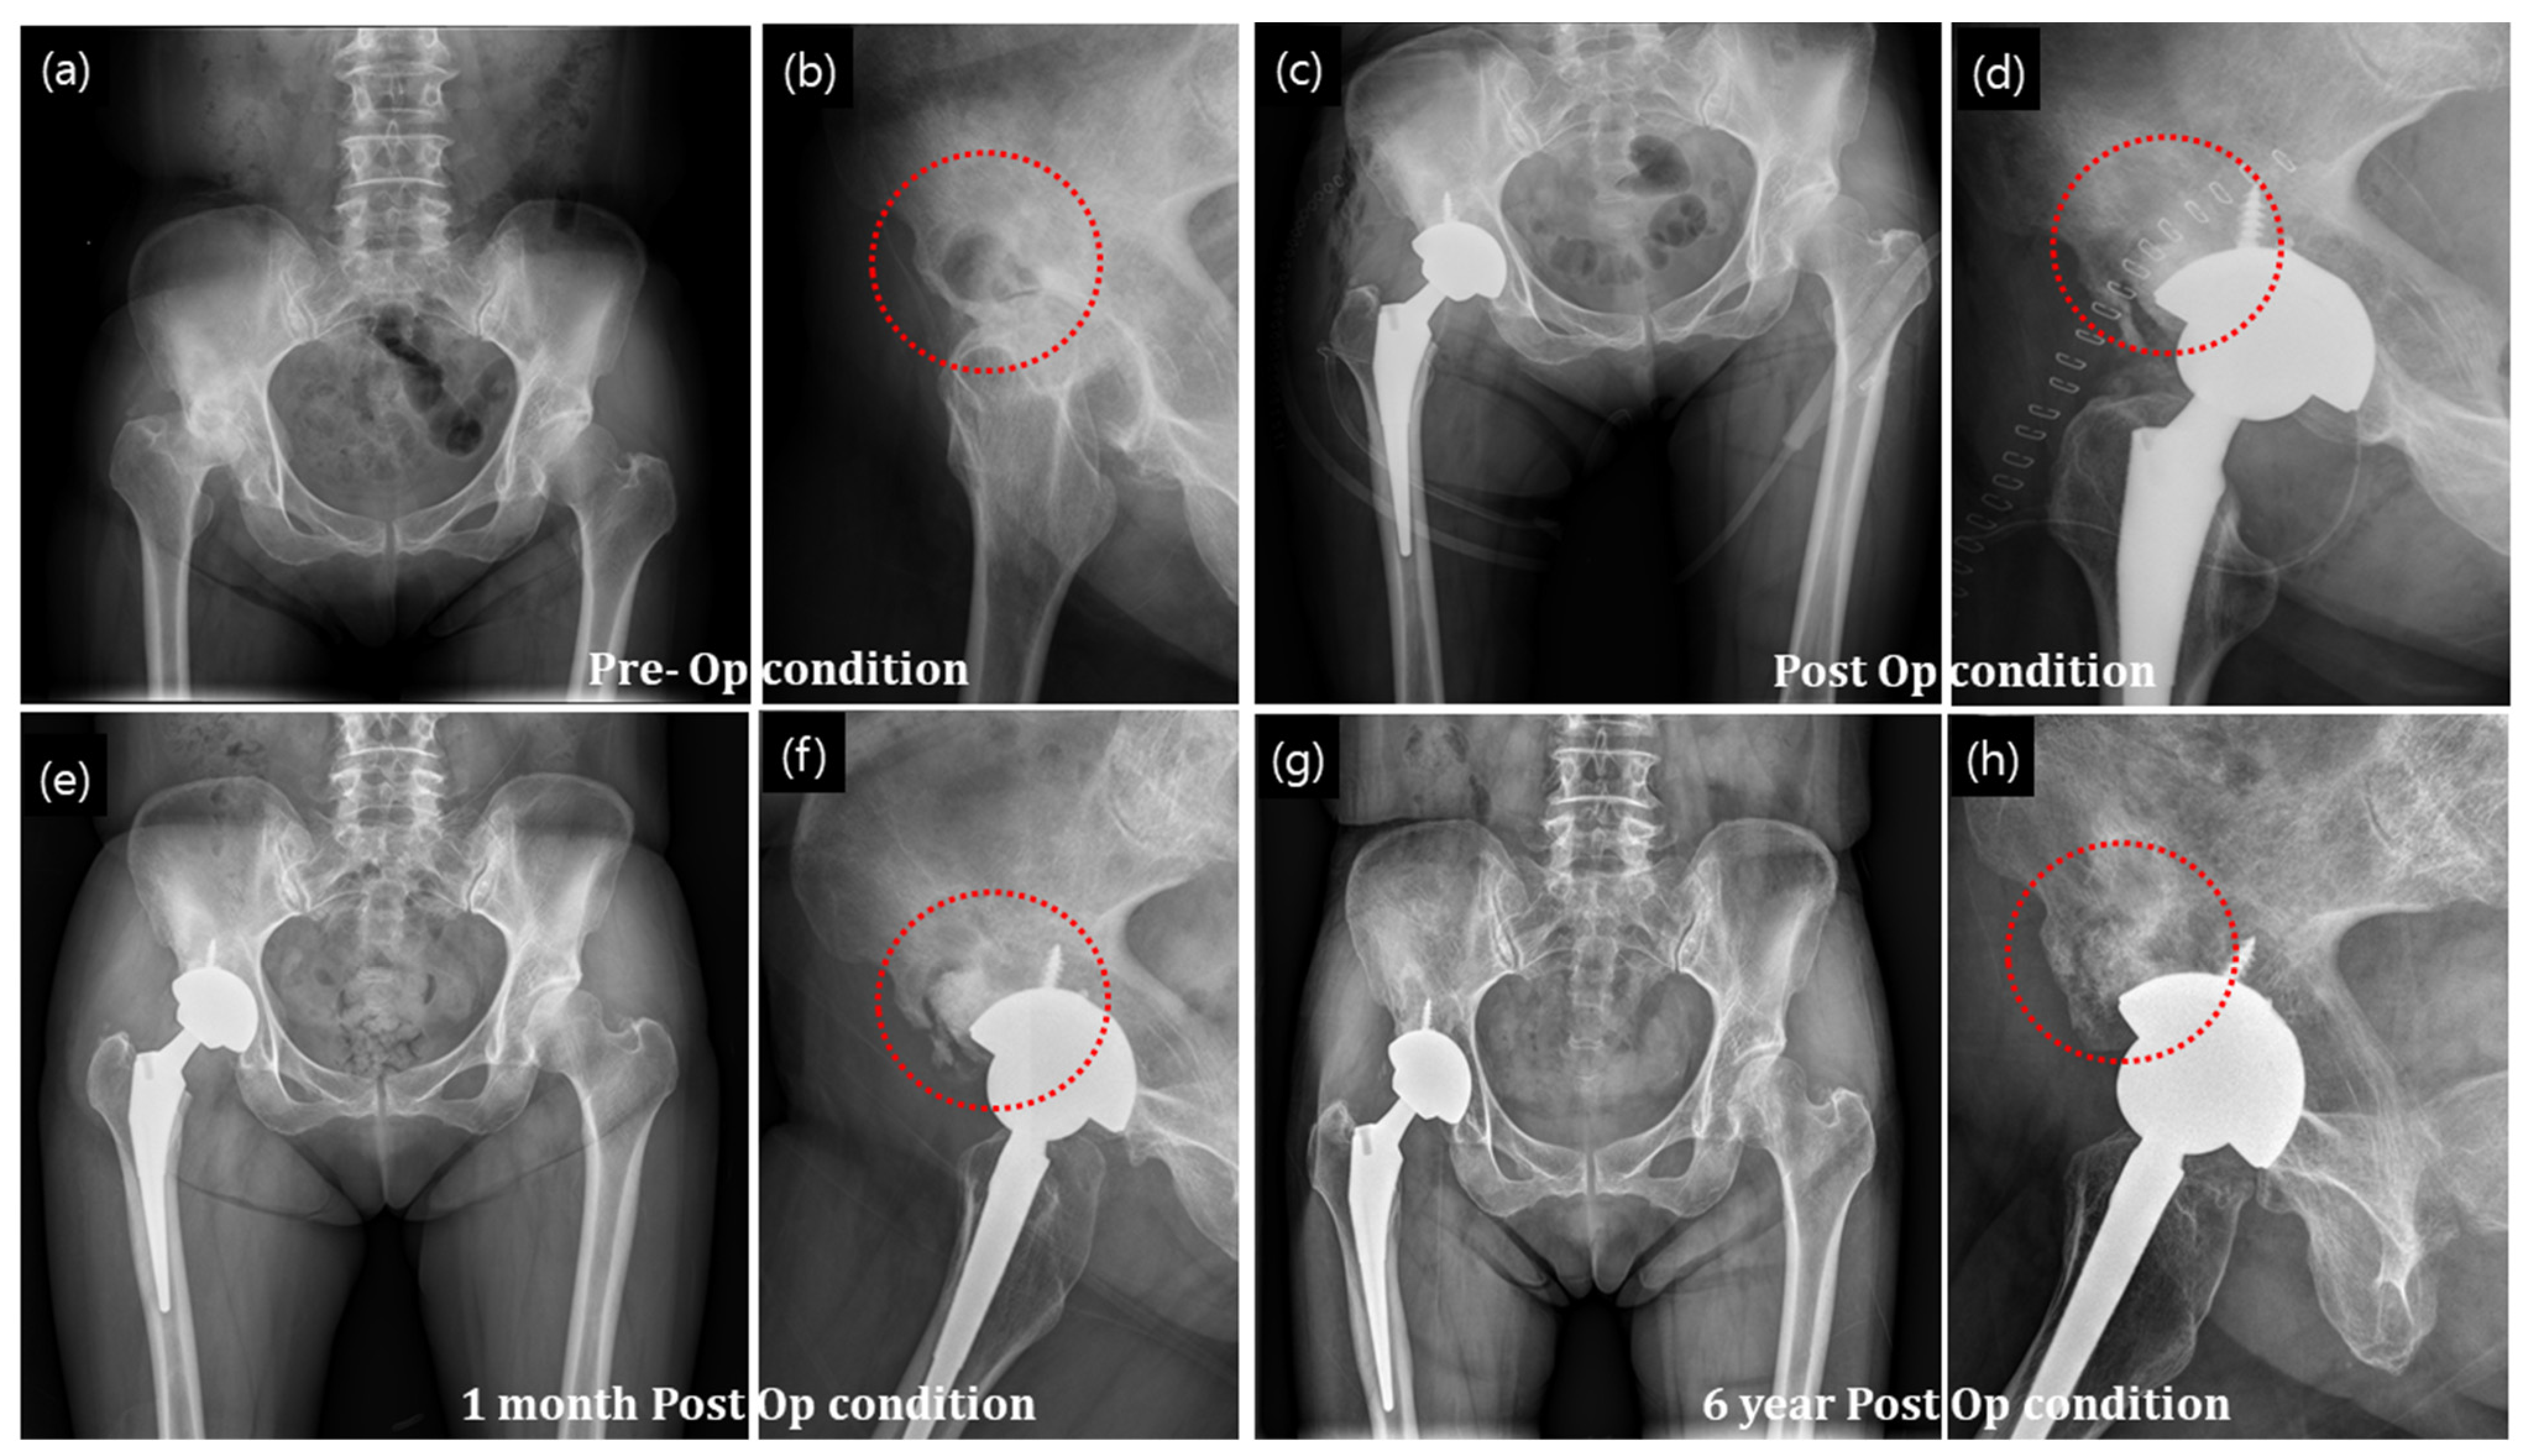

The radiographs in Figure 8a,b show avascular necrosis of the bilateral femoral head and 4 × 3 cm bony defect at the right anterosuperior aspect of the acetabulum. The necrosis extended and the femur head was damaged. Total hip replacement surgery was performed with an artificial hip joint, and the defect area with bone necrosis was filled with a granular bone substitute (Figure 8c,d). Bone regeneration was evident at 1 month postoperatively (Figure 8e,f). After 6 years postoperatively, bone formation significantly increased as indicated by the homogeneous contrast in Figure 8g,h. Host bone and newly regenerated bone integration was well maintained, except in some parts of the posterior acetabular region (shown as a shadowy line). Moreover, the radiographs show a well-maintained prosthetic device and complete filling of bony defect with granular bone substitutes. Promotion of bone regeneration by the granular bone substitutes without any complications was also observed.

Figure 8. Primary arthroplasty of the hip joint treated with granular bone substitute for restoration of new bone in the necrossed bone (a,b) X-ray of the bone with necrosis, (c,d) postop condition with application of granular bone substitute around the hip joint implant, (e,f) new bone formation at the granular bone graft site after one months of operation and (g,h) after 6 years of operation condition. The red circles indicate implanted defect zone.